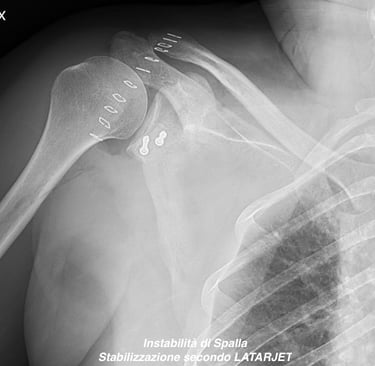

Instabilità di spalla

Gallery

Attività Chirurgica